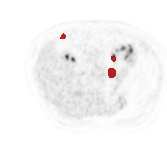

There has been growing research interest in using deep learning based method to achieve fully automated segmentation of lesion in Positron emission tomography computed tomography(PET CT) scans for the prognosis of various cancers. Recent advances in the medical image segmentation shows the nnUNET is feasible for diverse tasks. However, lesion segmentation in the PET images is not straightforward, because lesion and physiological uptake has similar distribution patterns. The Distinction of them requires extra structural information in the CT images. The present paper introduces a nnUNet based method for the lesion segmentation task. The proposed model is designed on the basis of the joint 2D and 3D nnUNET architecture to predict lesions across the whole body. It allows for automated segmentation of potential lesions. We evaluate the proposed method in the context of AutoPet Challenge, which measures the lesion segmentation performance in the metrics of dice score, false-positive volume and false-negative volume.